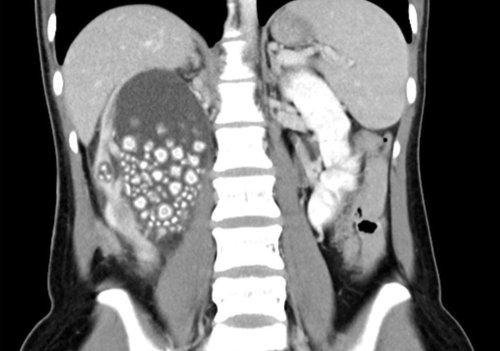

Tayvan'da sırt ağrısı şikayetiyle hastaneye başvuran 20 yaşındaki Xiao Yu’nun böbreklerinden 300’den fazla böbrek taşı çıkarıldı.

Tayvan’ın güneyinde yer alan Tainan şehrinde 20 yaşındaki Xiao Yu sırt ağrısı şikayetiyle hastaneye başvurdu. Yapılan tetkiklerin sonucunda böbreklerinde çok sayıda böbrek taşı tespit edilen Yu acil ameliyata alındı. Başarılı geçen ameliyatın ardından Yu’nun böbreklerinden 0.5-2 cm boyutlarında 300’den fazla böbrek taşı çıkarıldı.